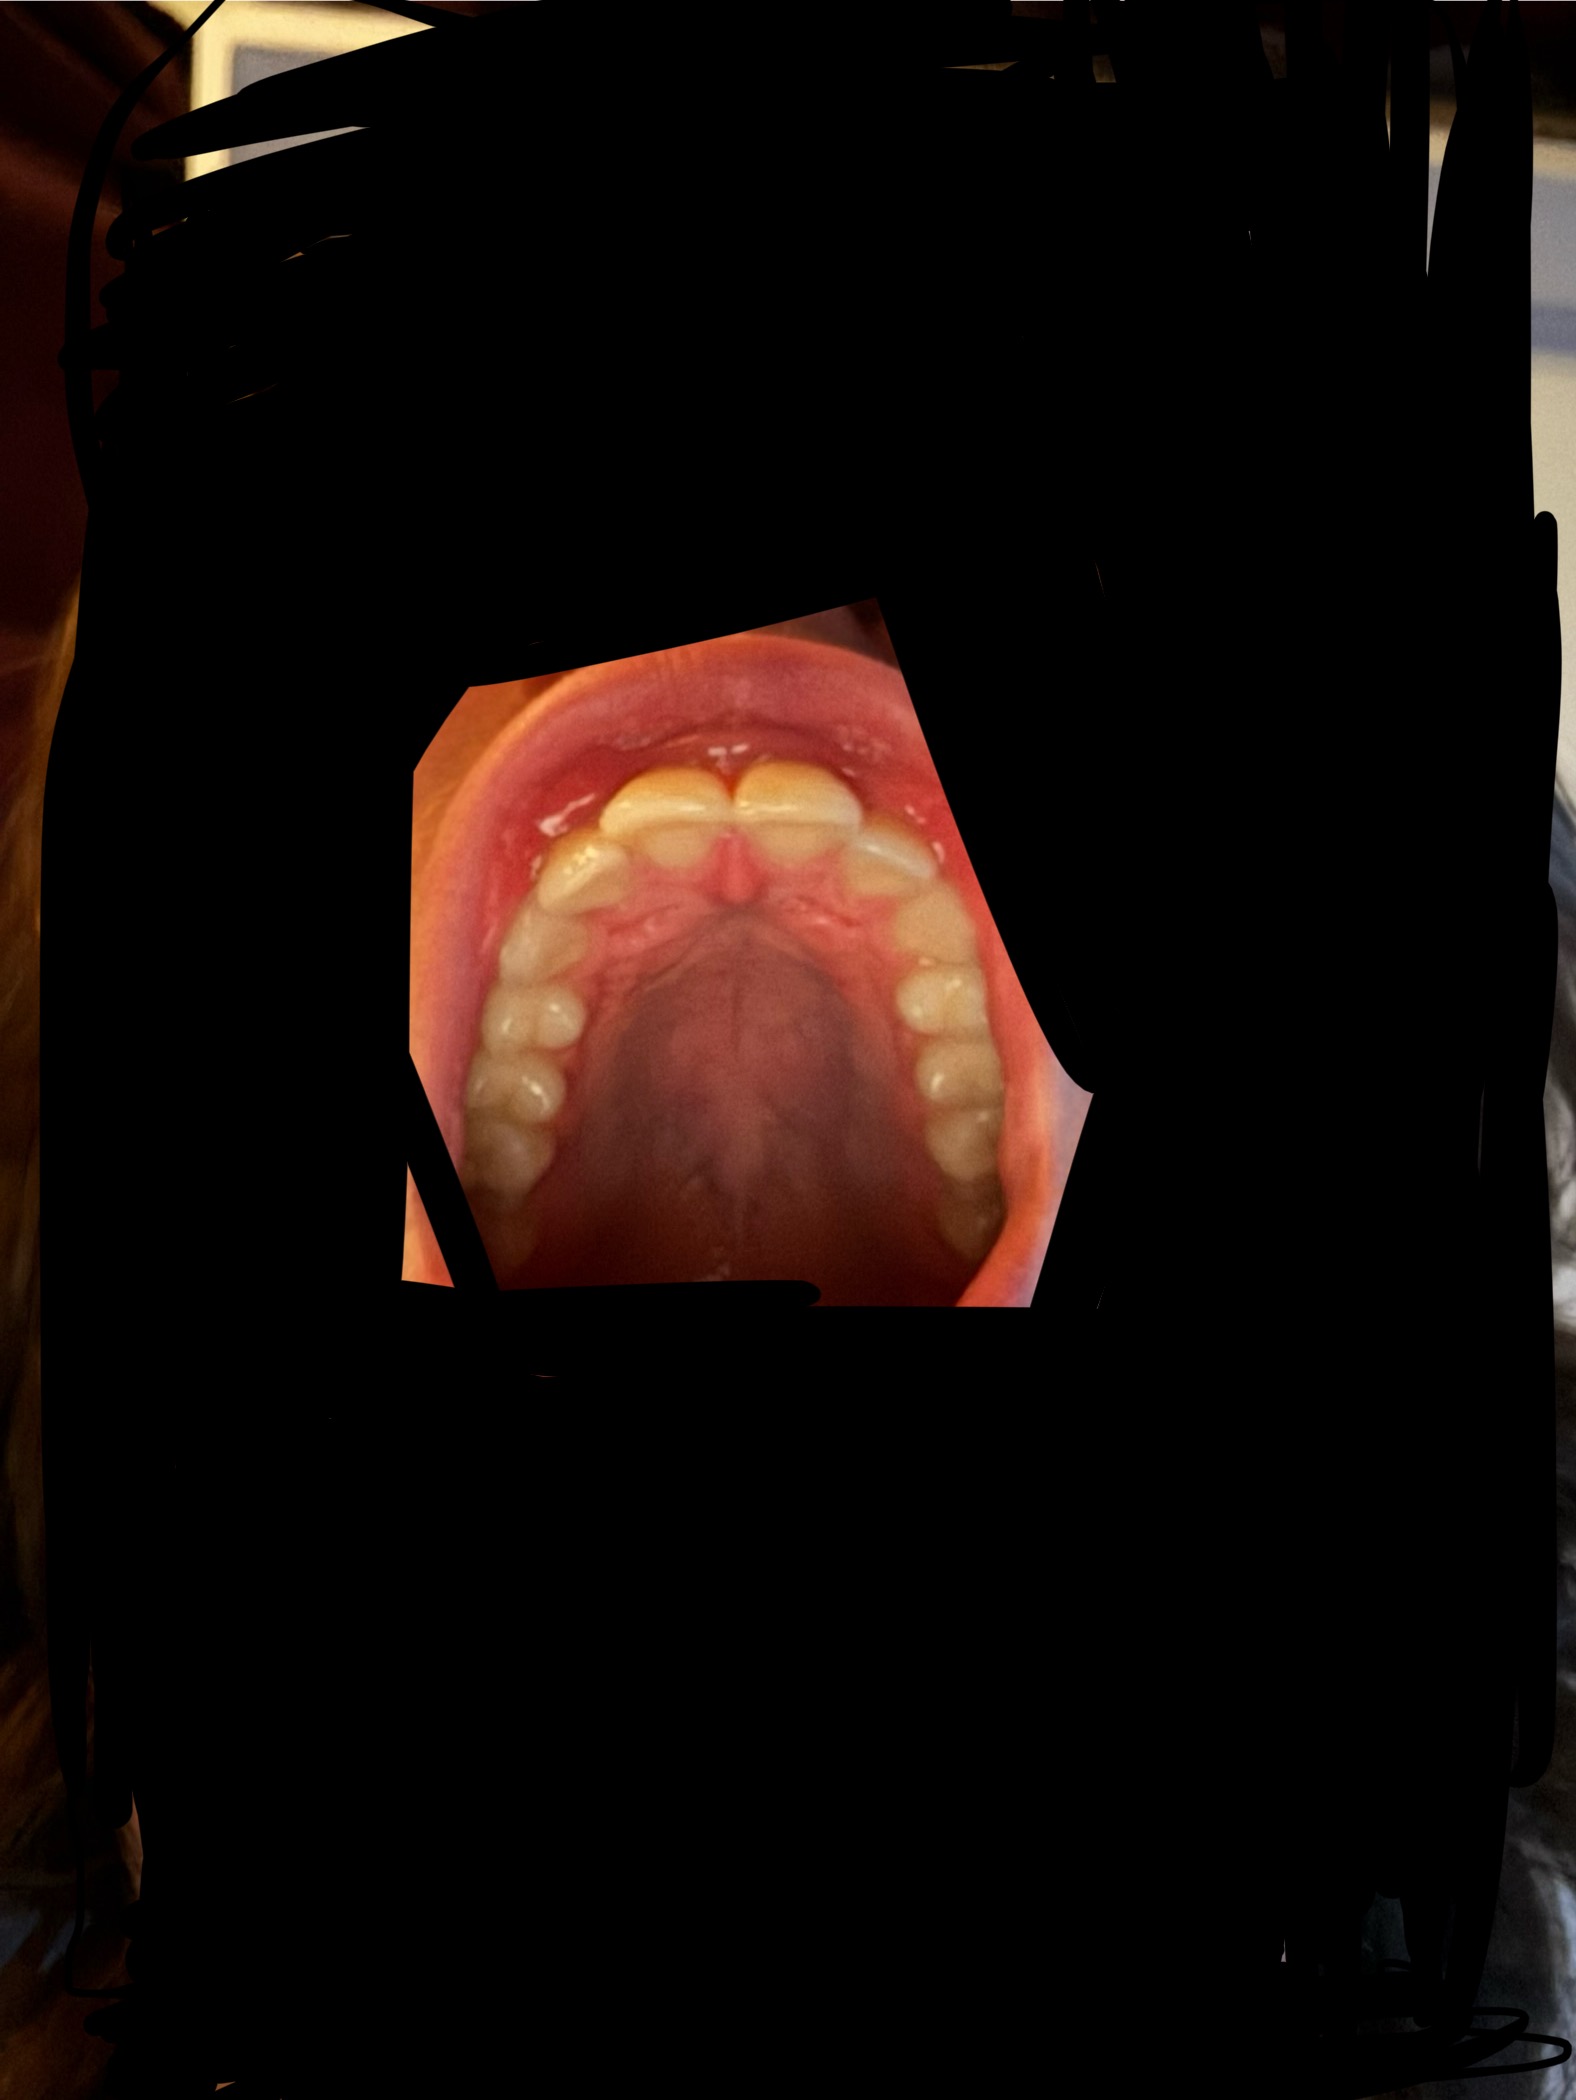

you should stfuView attachment 4320095View attachment 4320098View attachment 4320096 I have always had a short mandible and recessed chin since I was mouth breathing and malnourished since birth, I went to a dentist and got night braces that jutted my teeth forward. I have just got it confirmed that I should stop with it. Should I get a palate expander or braces or something else orthodontic related?